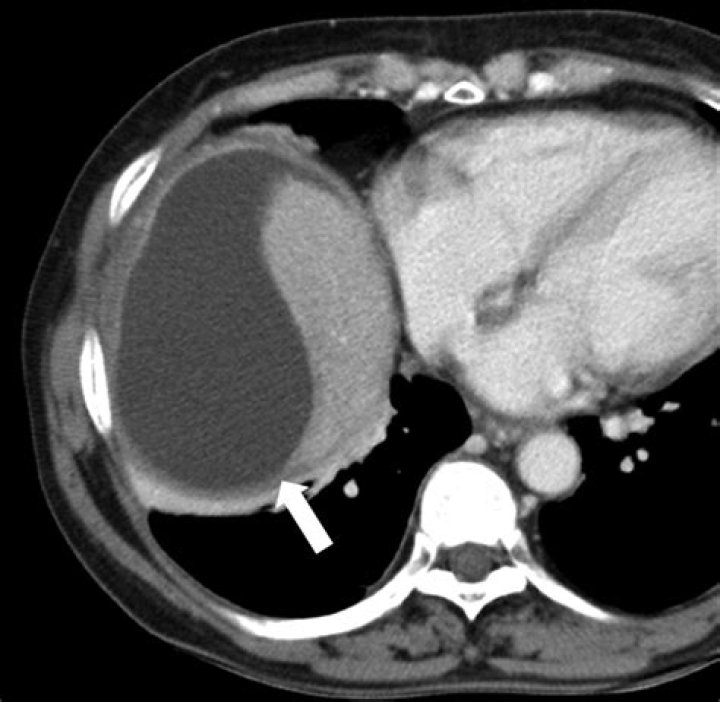

What is a liver Biloma

Biloma is collection of bile within the abdominal cavity. It happens when there is a bile leak, for example after surgery for removing the gallbladder (laparoscopic cholecystectomy), with an incidence of 0.3–2%. Other causes are biliary surgery, liver biopsy, abdominal trauma, and, rarely, spontaneous perforation.

A biloma is a rare abnormal accumulation of intrahepatic or extrahepatic bile caused by traumatic or spontaneous rupture of the biliary tree1, 2). It is most commonly caused by surgery, percutaneous transhepatic cholangiography (PTC), percutaneous transhepatic biliary drainage (PTBD), and abdominal trauma11, 12).

Abstract. The term biloma describes an encapsulated collection of bile within the abdomen, usually secondary to bile duct disruption. The commonest causes reported in the literature are iatrogenic (secondary to hepatobiliary surgery), trauma or complications due to choledocholithiasis.